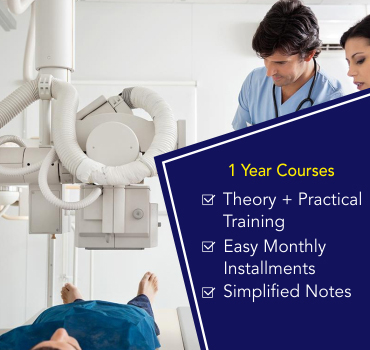

Best Training in

X-Ray TechnicianThis institue is known as one of the best paramedical institute for giving training & job placements to students in paramedical field. -